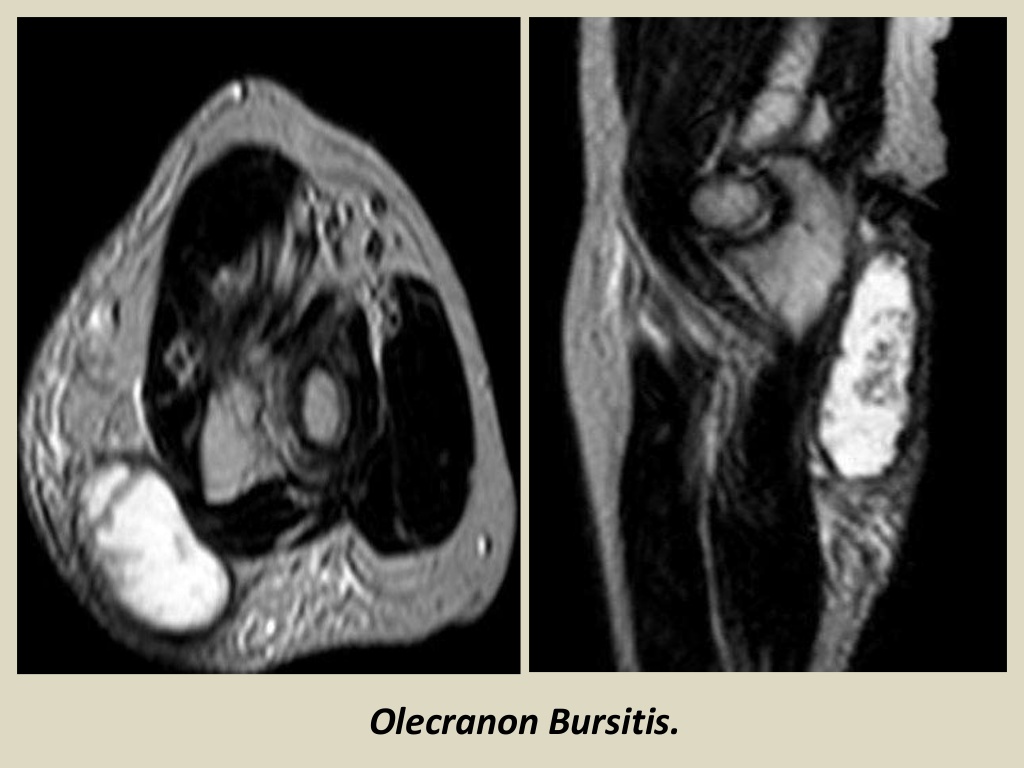

Olecranon bursitis Physio Check

MRI MusculoSkeletal Section Bursa of elbow joint. Elbow Bursitis Jiu Jitsu knees aren't the only things that take a beating in jiu jitsu. Learn more about the common elbow injuries you might encounter in bjj and. sustain a bjj elbow injury during training or competition? Here are few methonds to recover from elbow. It is caused by the. Learn which structure is most commonly injured. The bursae plays the. Elbow Bursitis Jiu Jitsu.